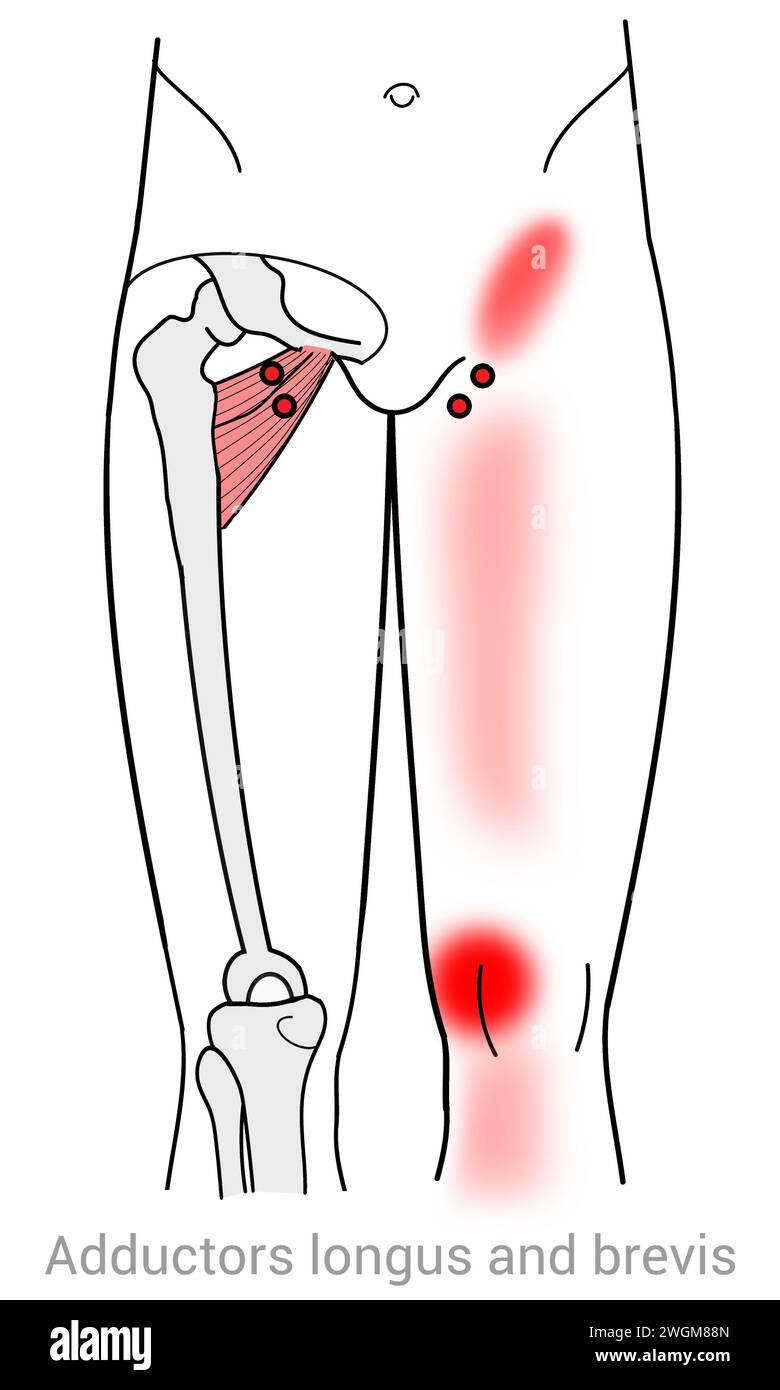

Adductors Longus & Brevis : points de déclenchement myofasciaux et localisations douloureuses associées Banque D'Imageshttps://www.alamyimages.fr/image-license-details/?v=1https://www.alamyimages.fr/adductors-longus-brevis-points-de-declenchement-myofasciaux-et-localisations-douloureuses-associees-image595432565.html

Adductors Longus & Brevis : points de déclenchement myofasciaux et localisations douloureuses associées Banque D'Imageshttps://www.alamyimages.fr/image-license-details/?v=1https://www.alamyimages.fr/adductors-longus-brevis-points-de-declenchement-myofasciaux-et-localisations-douloureuses-associees-image595432565.htmlRF2WGM88N–Adductors Longus & Brevis : points de déclenchement myofasciaux et localisations douloureuses associées